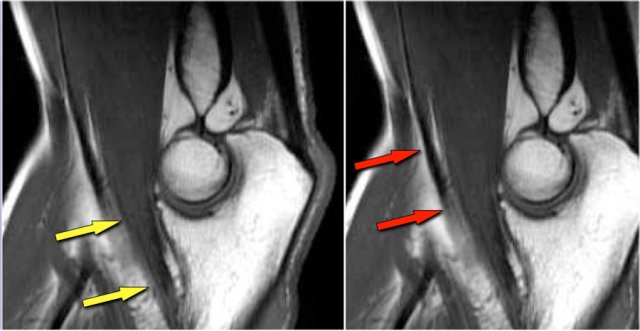

Elbow dislocation

Here a lateral view of the elbow of a patient who fell on the outstretched arm.

The radiograph shows joint effusion (red arrows) and a coronoid fracture (yellow arrow).

Continue with the MR-images.

Now here is the MR.

Study the images and then continue reading...

Coronal view:

1. Lateral collateral ligament is completely stripped (yellow arrow).

2. radial head is subluxed.

3. marrow edema of the coronoid process due to the fracture (red arrow).

Sagittal view:

1. Radial head is a little bit subluxed posteriorly (yellow arrow).

2. Large effusion and capsular disruption posteriorly.

3. Contusion of the posterior side of the capitellum as a result of impaction by the coronoid process (red arrow).

All these signs are the result of a posterior dislocation.

These images are of a 23 year old male who fell onto his outstretched hand two weeks ago while skateboarding.

On physical exam there was decreased range of motion of the elbow and tenderness along the lateral aspect.

First study the images, then continue reading...

What is the structure on the axial image behind the radial head?

• Again the characteristic pattern of marrow edema that is seen in posterior elbow dislocation with contusion in the anterior side of the radial head (red arrow) and on the posterior side of the capitellum.

• The radial head must have hit the posterior part of the capitellum.

The structure behind the radial head is the annular ligament.

It is irregular and thickened as a result of the posterior dislocation.